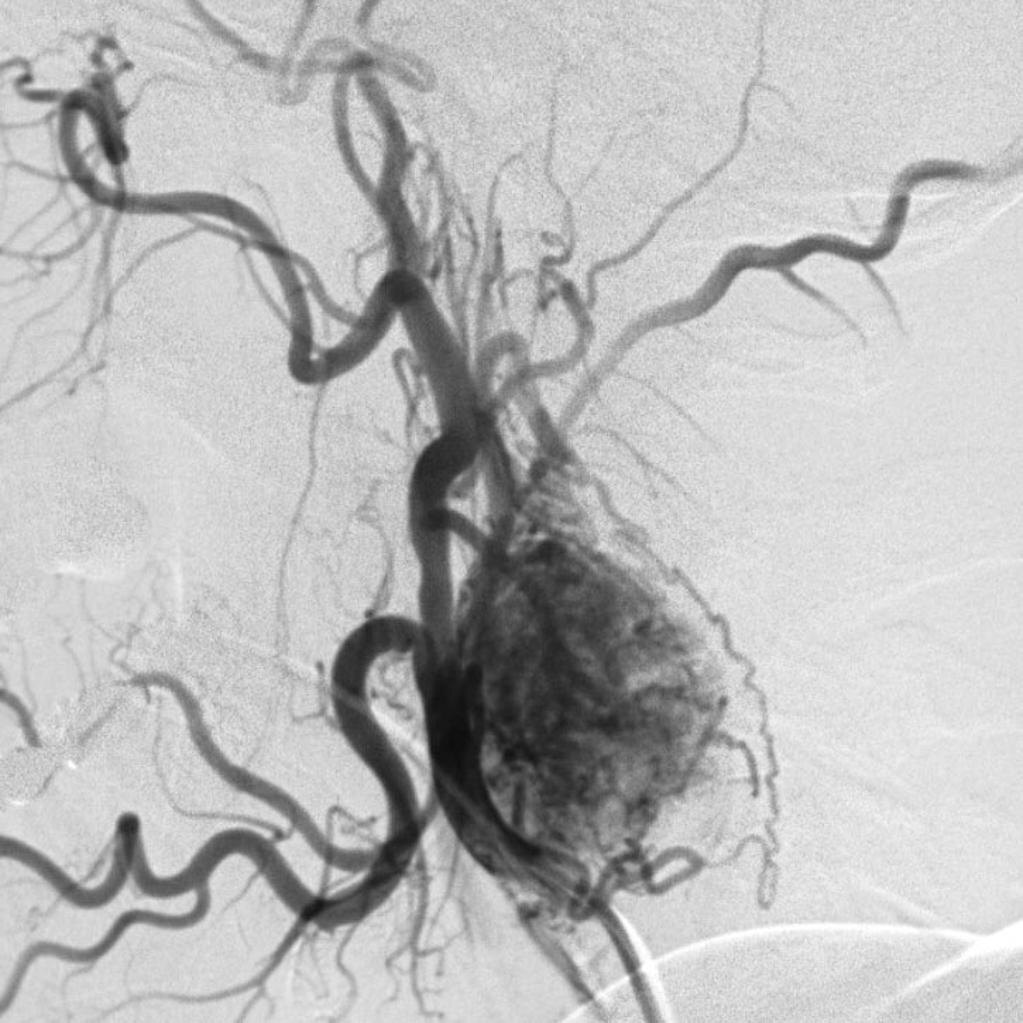

Ангиографическая картина хемодектомы каротидного синуса. Изображение из открытых источников.

Диагностика: При аускультации выявляется систолический шум. При надавливании на опухоль возможно кратковременное снижение артериального давления и появления бледности кожи. Основные инструментальные методы визуализации хемодектом шеи являются каротидная ангиография (рентгеновское исследование) и УЗ-допплерография/дуплексное сканирование. Также, применяются МСКТ и МРТ шеи с контрастированием. Биопсия опухоли не проводится из-за угрозы фатального кровотечения.